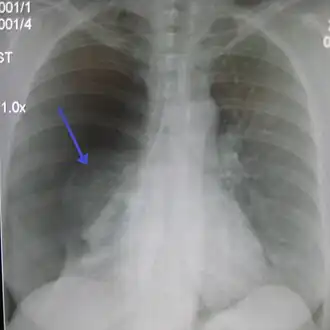

La radiographie du thorax de face permet de faire, en règle générale, le diagnostic, sous forme d'une clarté d'un sommet (ou péri hilaire dans les cas plus important) avec visualisation d'un fin liseré convexe vers le haut, correspondant au poumon rétracté. Dans les cas difficiles, on peut s'aider d'une radiographie prise en expiration. La présence simultanée d'un épanchement liquidien donne l'aspect de niveau hydro-aérique rectiligne horizontal caractéristique.

Bien que la radiologie ne détecte pas toujours les pneumothorax, la première ligne de soin exige une radio de face en respiration normale puis, si le cliché est non contributif en inspiration forcée, une tomodensitométrie (scanner) si poumon pathologique.